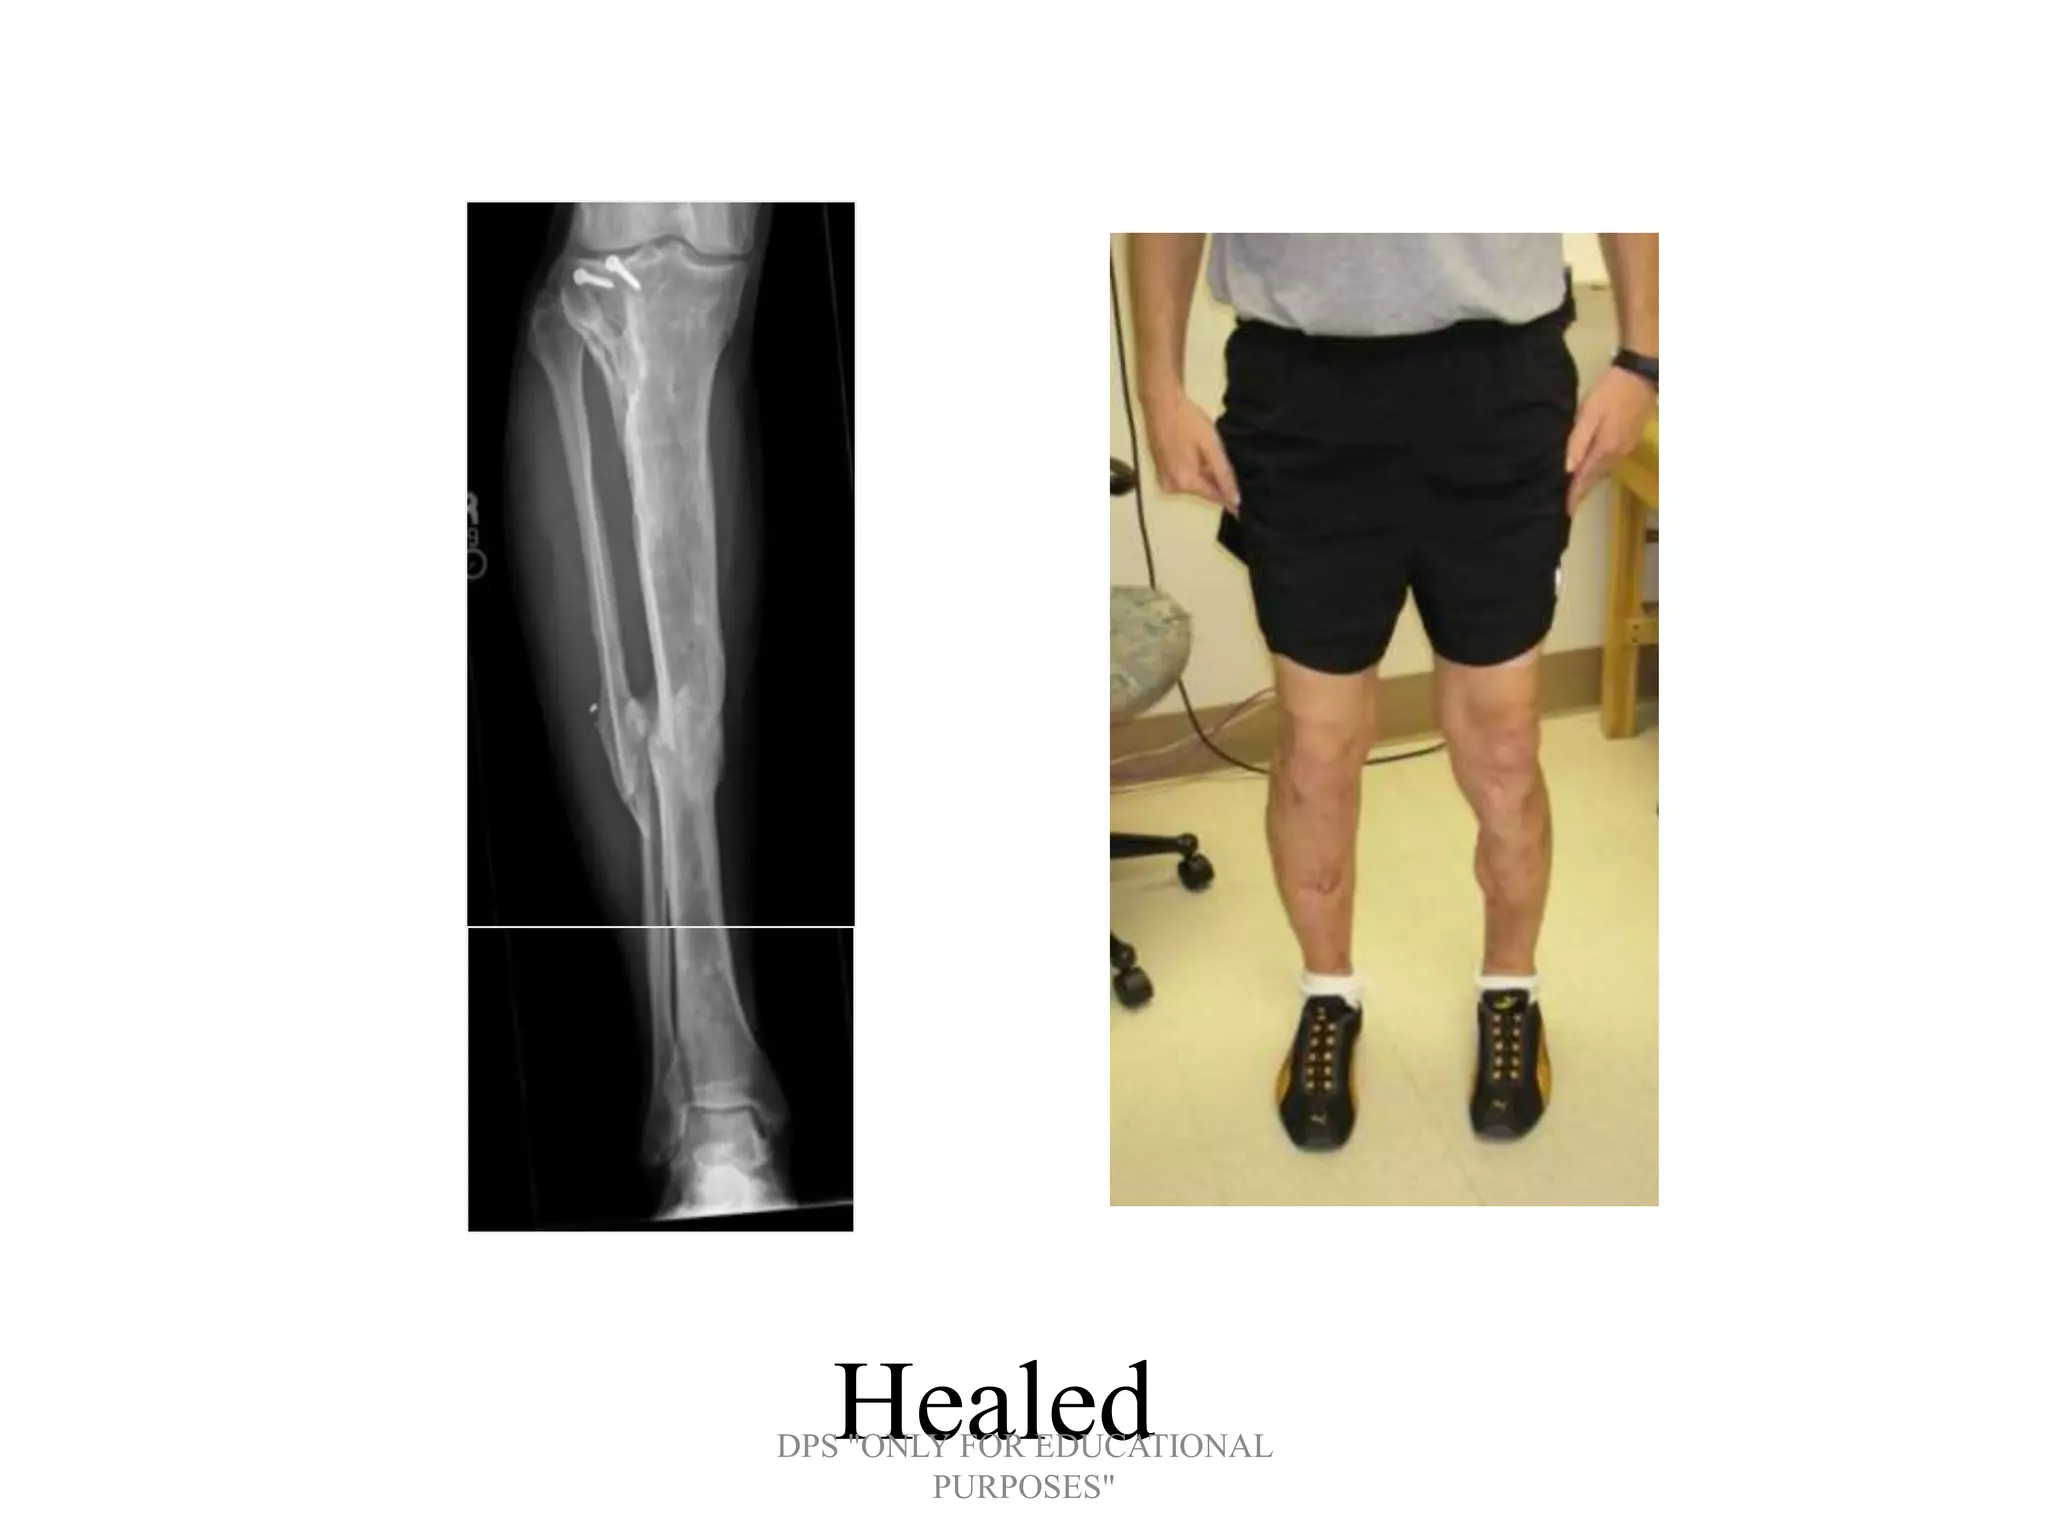

• 3B tibia with segmental bone loss, 3A

• Convert to circular

and distractionDPS "ONLY FOR EDUCATIONAL

• Consolidation

HealedDPS "ONLY FOR EDUCATIONAL